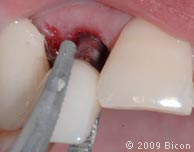

26. Для раскрытия верхнего бокового правого резца сделан надрез.

27. Извлечение заглушки с помощью специального инструмента.